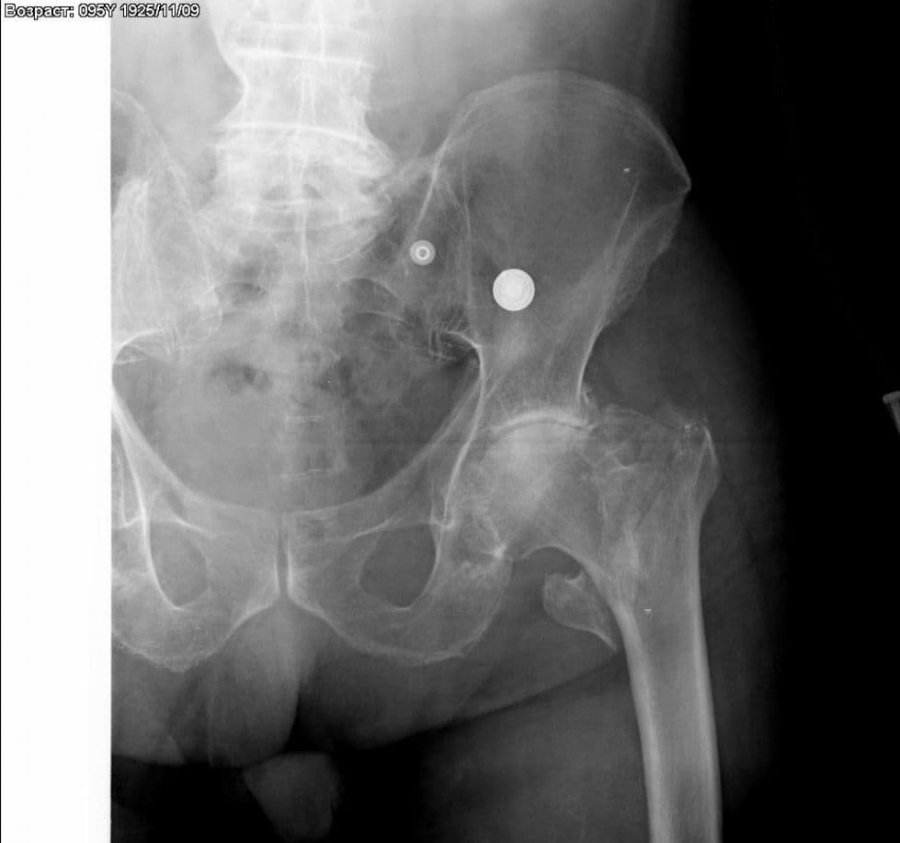

В травматологическое отделение Каширской центральной больницы поступил 95-летний мужчина с травмой тазобедренного сустава, которую он получил в результате падения. Как уточнили в учреждении, у ветерана Великой Отечественной войны был диагностирован чрезвертельный перелом бедра.

«Это тяжелое травматическое повреждение. И считается более благоприятным повреждением по сравнению с переломом шейки бедра, поскольку при этой травме возможно самостоятельное сращение. Тем не менее, такая травма в преклонном возрасте представляет большую опасность даже при хороших перспективах излечения. Поэтому выбор лечебной тактики с учетом состояния и возраста пациента в данном случае важен не меньше, чем при переломах шейки бедра», – рассказал заведующий травматологическим отделением Денис Фомин.